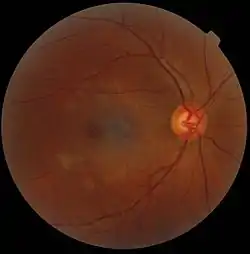

%252C_an_artefact.jpg.webp)

In microscopy, an artifact is an apparent structural detail that is caused by the processing of the specimen and is thus not a legitimate feature of the specimen. In light microscopy, artifacts may be produced by air bubbles trapped under the slide's cover slip.[1]